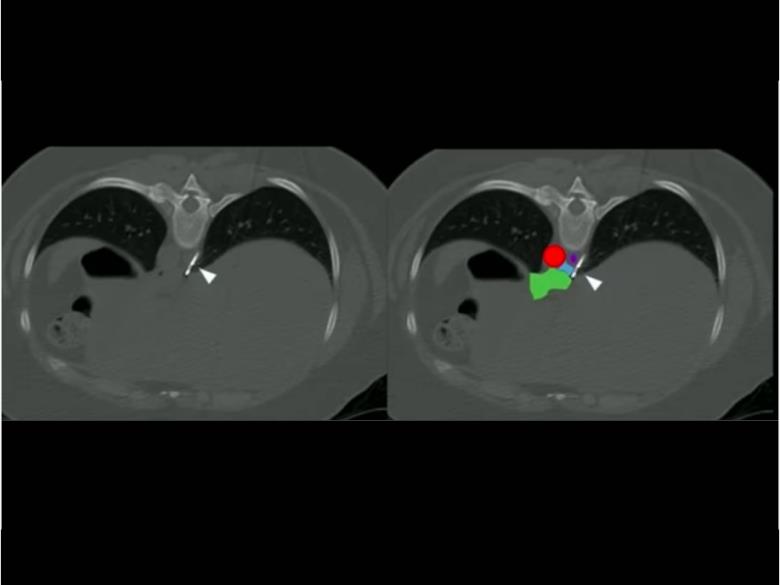

為了做到這一點,他們使用了電腦斷層機器,在每個病人的背部刺入針管,引導輸送氬氣、冷凍住迷走神經後干。利用10名身體質量指數(BMI)落在30~37的受試者接受這為期90天的實驗。治療結束時,所有人都表示食慾有所下降,平均體重也降低了3.6%、身體質量指數平均下降近14%,並且過程中未發現併發症,迄今也沒有出現不良反應。